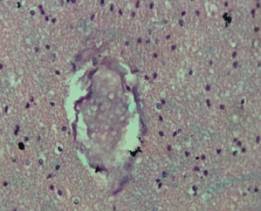

В ткани головного мозга имелись признаки отека и

центра, нарастающим отеком легких и поражениями сердца[8]. Гистологически,

помимо отека дренажной глии, проявляющегося микроскопически периваскулярным и

перицеллюлярным отеком (Рис.1 .), выявлены разнообразные нарушения

микроциркуляции в виде стаза эритроцитов в капиллярах, общего венозного

полнокровия, пареза резистентного звена микроциркуляции, сладжа эритроцитов,

иногда образования фибриново-эритроцитарных тромбов и множественные мелкие

диапедезные кровоизлияния в субкортикальных отделах и в стволе, наблюдавшиеся в

53% случаев.

Рис.1.

Б-ной В., 22г. Стаж героиновой наркомании 3г. Парез и полнокровие микроциркуляторного

русла, эритроцитарно-фибриновые тромбы в капиллярах субкортикальных отделов

головного мозга при ДВС-синдроме.

Окраска

гематоксилин-эозин. х 100